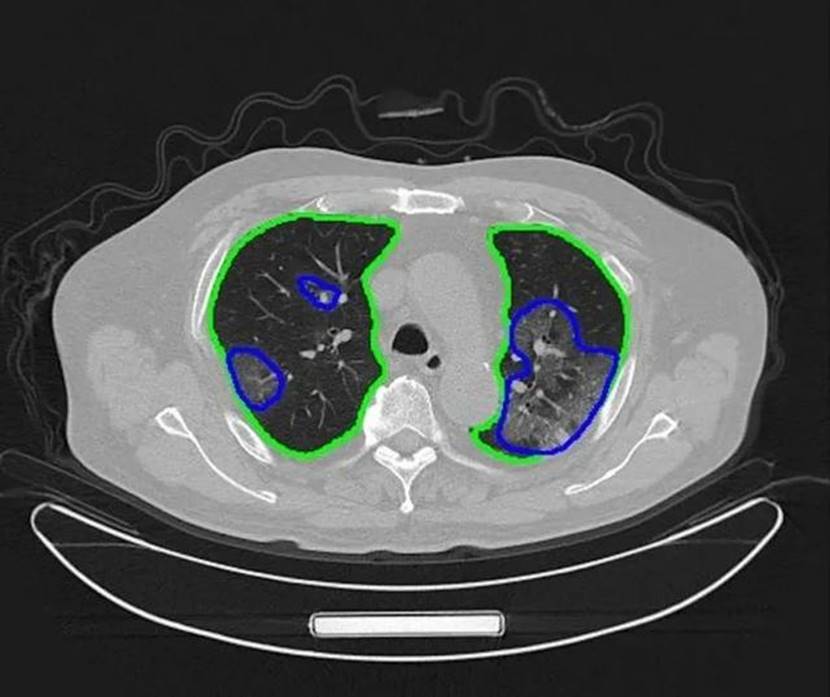

騰訊覓影AI助力秒級識別新冠肺炎

疫情發生,“騰訊覓影”第一時間啟動“基于CT影像的新冠肺炎AI輔助診斷”專項,在AI輔助診斷肺炎分型的基礎上,利用騰訊天衍實驗室的深度學習技術以及自監督學習方法,在低訓練數據依賴下快速開發出新冠肺炎影像識別模型。在騰訊基金會支持,騰訊AI醫學影像科研力量和騰訊云技術助力下,湖北最大方艙醫院武漢日海方艙醫院、武漢協和西院、洪湖市人民醫院,用上人工智能CT設備,只需數秒,AI即可幫助前線醫生識別新冠肺炎。